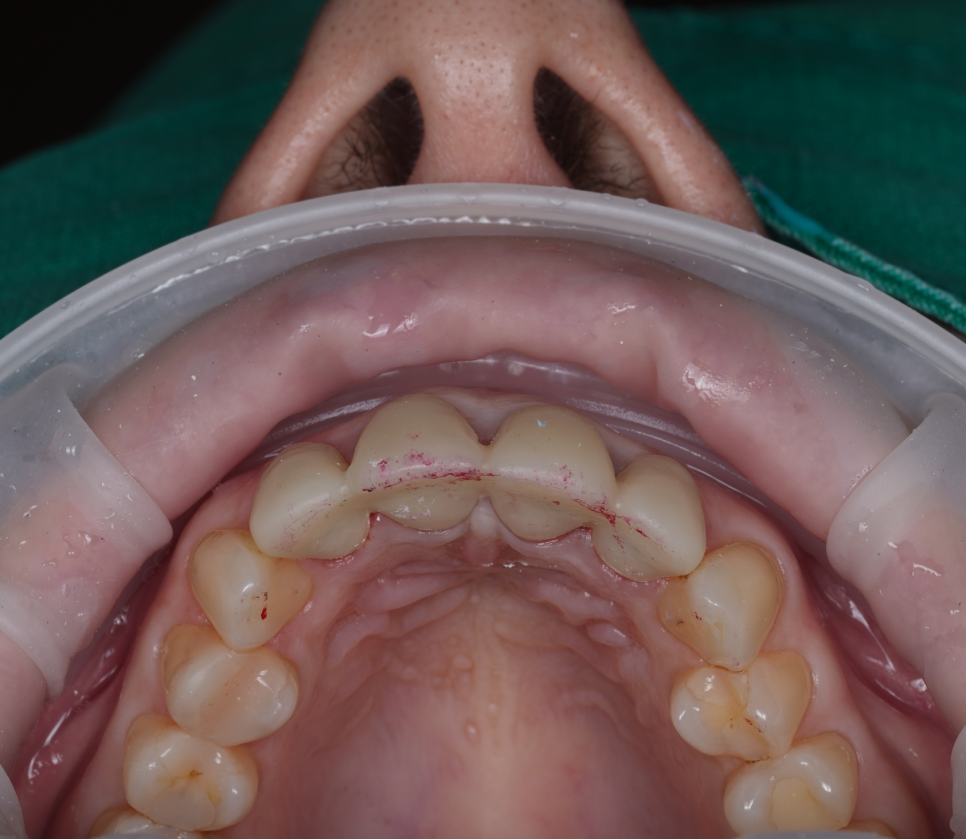

앞니 4개는 모두 브릿지로 한 덩어리로 연결되어 있었어요.

촬영 : 251015

겉보기엔 단단해 보이지만 실제로는 잇몸이 답답하게 눌리고 치아 사이 위생 관리도 어려운 구조라 가급적이면 하나씩 제작하는 싱글 크라운(Single Crown) 형태가 좋습니다.